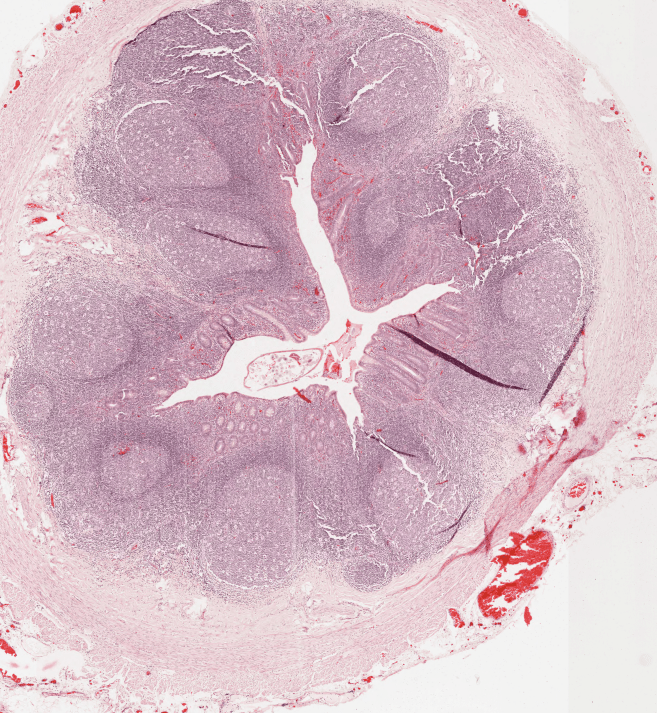

BAZO

Órgano linfoide 2° (secundario)

Encapsulado, carece de corteza y médula. Se encarga de eliminar células senescentes.

Pulpa blanca: nódulos linfáticos + PALS.

Pulpa roja:encargada de filtrar la sangre + Cordones de Billroth.

El bazo es un órgano encapsulado encargado de la eliminación de células senescentes, entre ellas los eritrocitos.Observe que el bazo carece de corteza y médula. Se organiza en pulpa blanca y pulpa roja.Se observa la cápsula de TCDi en contacto con la luz y la organización del bazo.Identifique las arteriolas centrales características de los nódulos linfáticos en el bazo.Arteriola central, Bazo, HyE.Las Vainas Linfáticas Periarteriolares (PALS) son cúmulos del Linfocitos T que rodean la arteriola central.La pulpa esplécnica nos permite identificar la organización del bazo, esta se divide en blanca y roja.Observe el nódulo linfático secundario, con su centro germinal, su zona del manto y una arteriola central.Bazo, HyE.Bazo, HyE.Bazo, Tinción de Giemsa.La arteriola central no siempre es «central», recuerda que puede ser desplazada por los linfocitos presentes en el nódulo linfático.Con impregnaciones argénticas podemos observar fibras reticulares (Colágena III)Delimitado con la línea negra podemos observar un nódulo linfoide secundario y señalado con la flecha negra observamos una arteriola central.Identifique.Identifique la arteriola central. Bazo, Tinción de Giemsa.Bazo de ratón, HyE.Identifique en la parte superior de la fotomicrografía la cápsula del bazo.